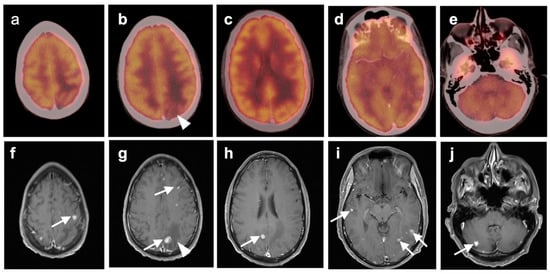

3.3. Primary Brain Tumors

3.4. CNS Lymphoma

3.5. Brain Metastases

3.6. Response to Therapy

3.7. Meningioma